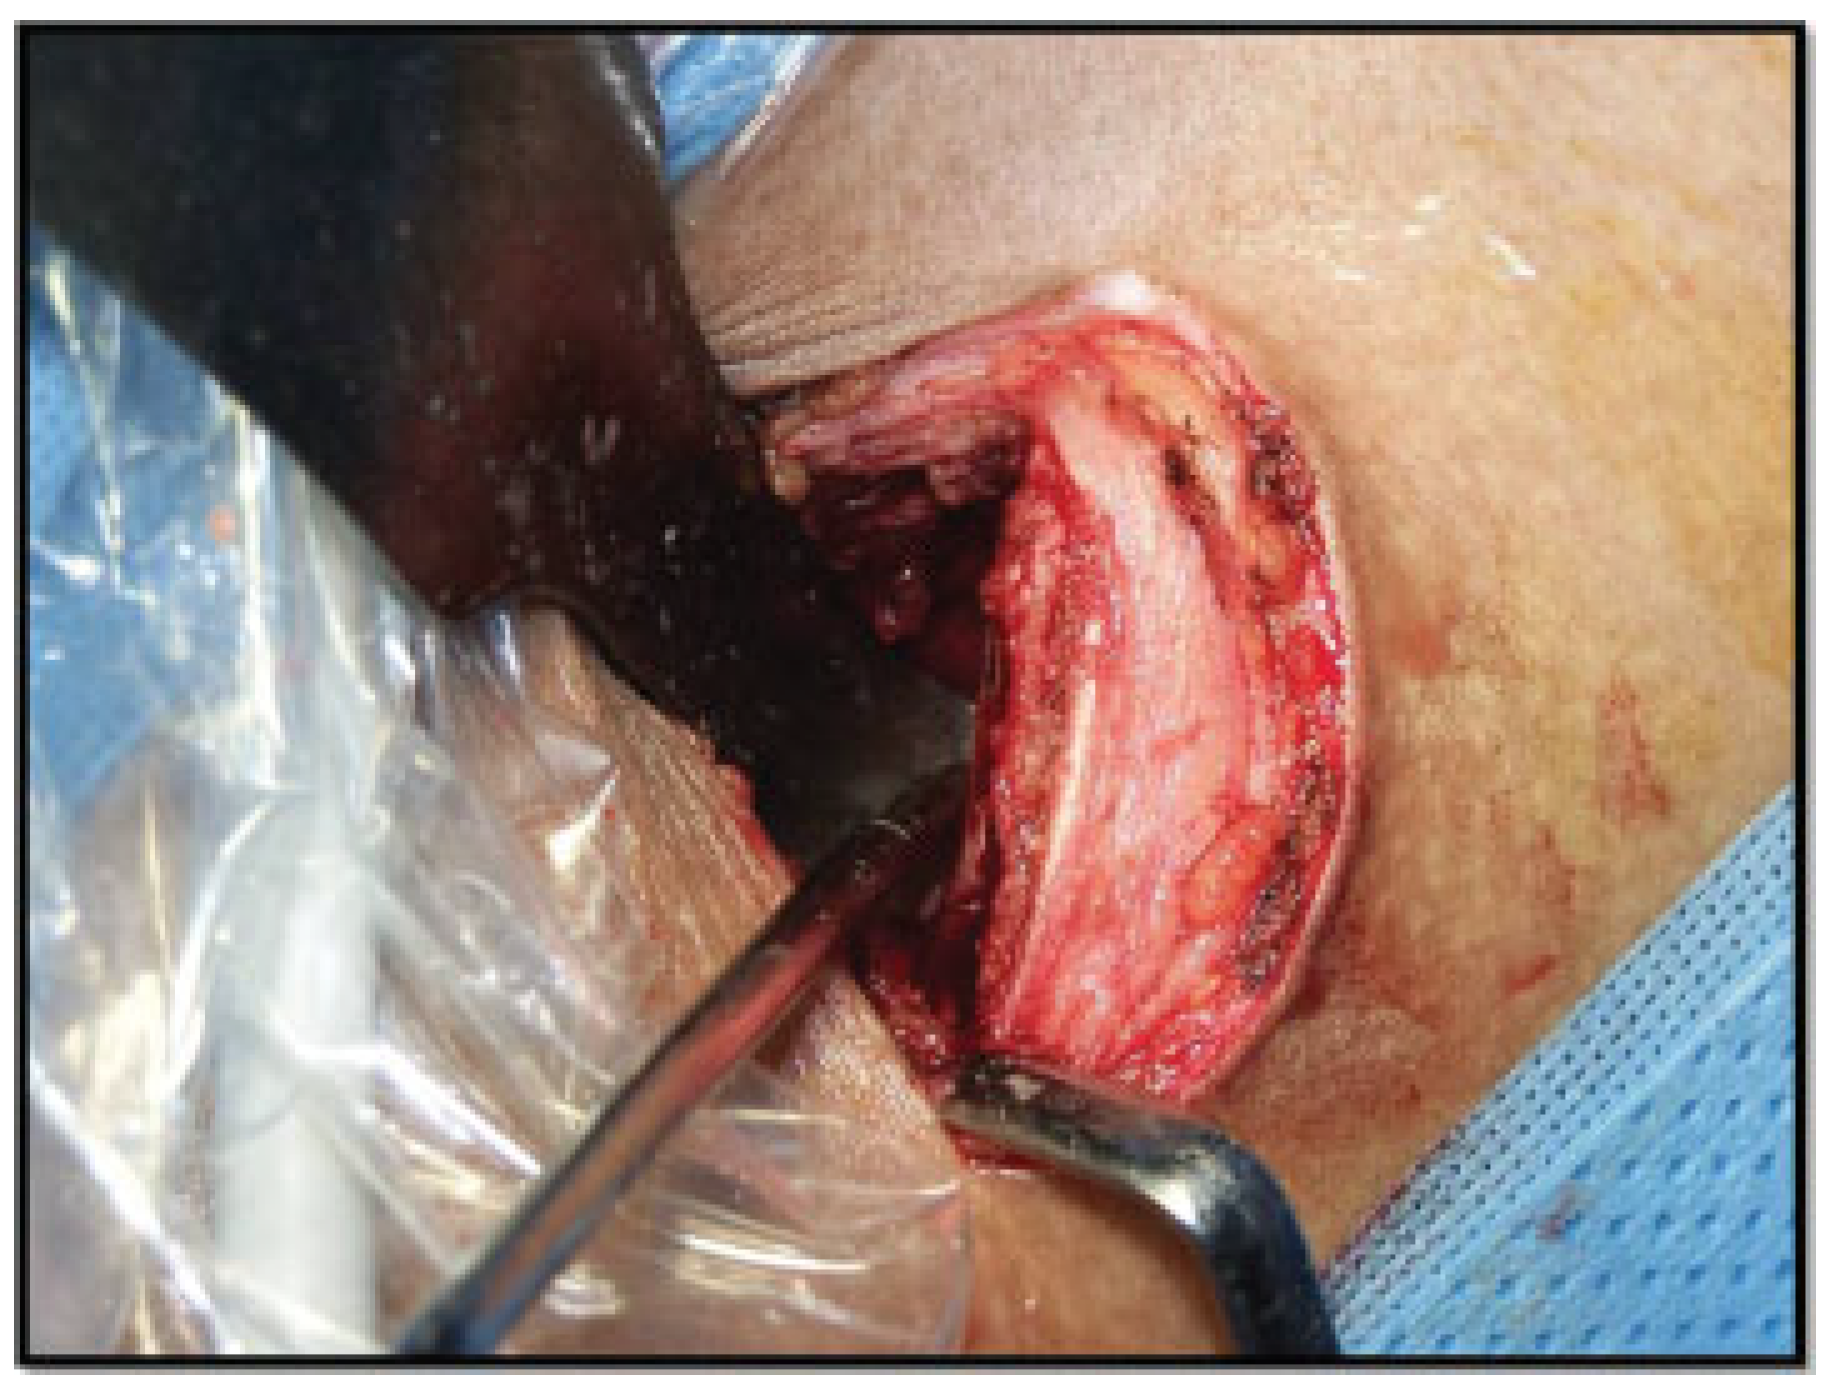

Surgical Technique